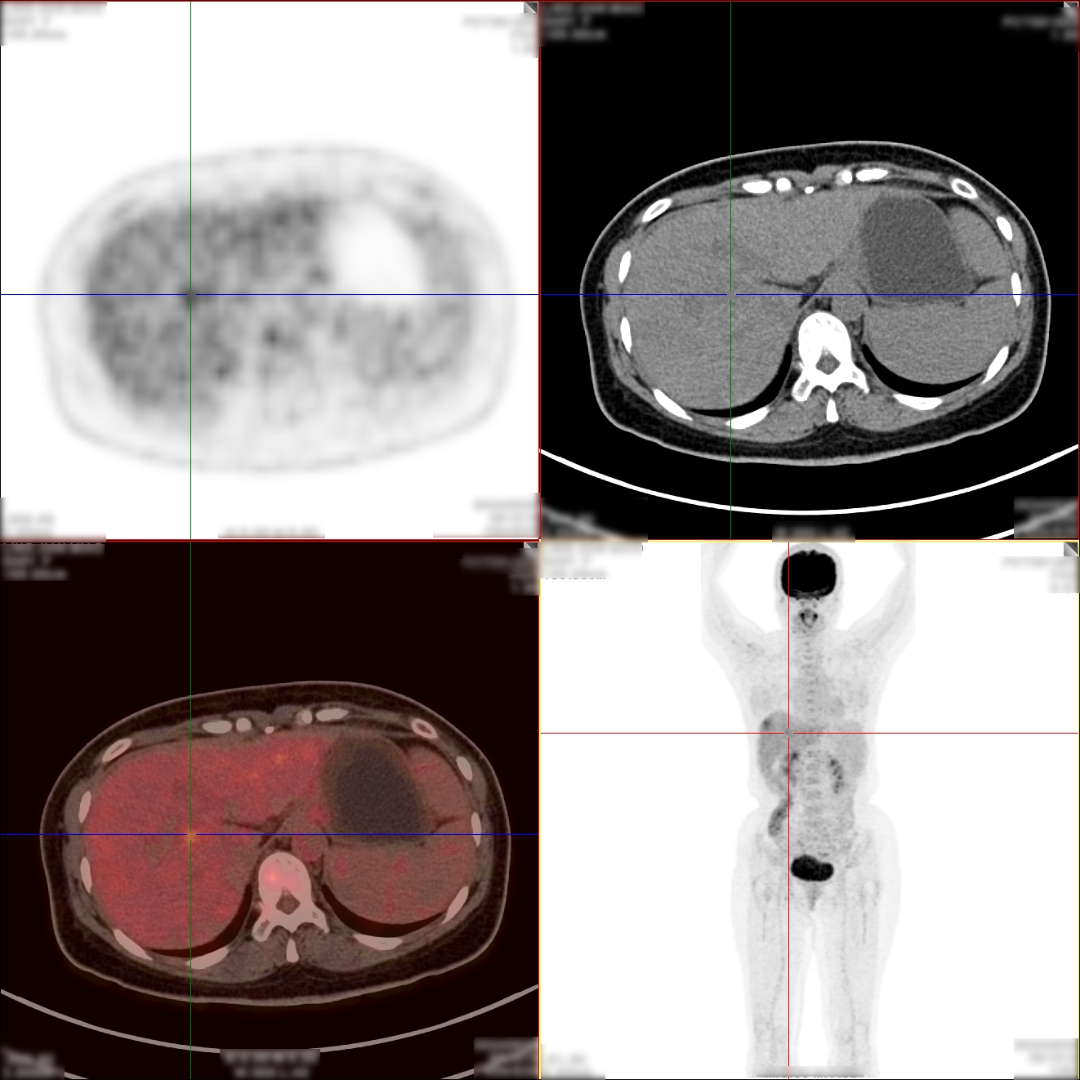

病史:女,48岁,无明显不适,健康查体,无特殊病史及手术史。乙肝大三阳,AFP:380.21ng/mL,CA199:33.24U/ml,CA125、CA153、CA724、 CEA(-)。

PET/CT检查所见

1、肝 S8 段见 1 个稍低密度软组织肿块,病灶内部分组织代谢增高,考虑肝细胞肝癌;

2、肝 S8 段另见 1 个稍低密度结节,代谢轻度增高,考虑为小肝癌或肝内子灶形成,该压迫相邻肝中静脉。

PET/CT活检病理:原发性肝癌